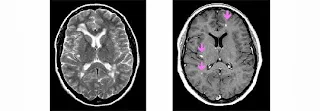

Omniscan, nome commerciale della gadodiamide, è un mezzo di contrasto contenente gadolinio che è utilizzato nella RMI per esaminare il cervello, la colonna vertebrale ed altre parti dell’organismo.

E’ anche utilizzato per identificare la malattia arteriosa coronarica (malattia delle arterie del cuore ) che può condurre ad attacchi cardiaci. Omniscan è somministrato per iniezione endovenosa e la dose raccomandata per gli adulti è di 01mmol/kg peso corporeo

La Risonanza Magnetica per Immagine è una moderna tecnologia che permette ai medici di avere una visione dettagliata di varie parti del corpo come il cervello,il midollo spinale ed il cuore. Per effettuare questo esame è necessario l’utilizzo di un mezzo di contrasto. I mezzi di contrasto per la RMI sono comunemente usati per visualizzare strutture anormali o lesioni del nostro corpo. I mezzi di contrasto contenenti gadolinio per la RMI sono soluzioni acquose che si iniettano nell’organismo per migliorare la qualità dell’immagine ed avere una visione più dettagliata dell’immagine. I mezzi di contrasto a base di gadolinio, un metallo raro che si estrae dalla terra, sono stati autorizzati per la prima volta nell’Unione Europea nel 1980. Poiché il gadolinio è altamente tossico, nella soluzione del mezzo di contrasto è legato reversibilmente a una struttura complessa con altre molecole, chiamata chelato